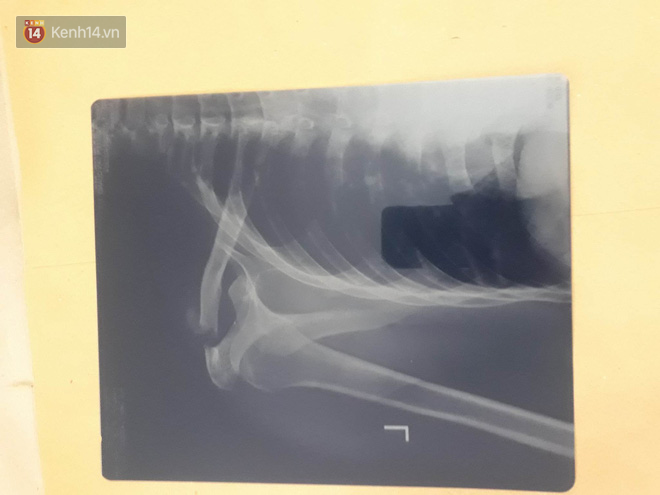

Là một trong số những nhân viên trên tàu SE19 bị thương sau vụ việc, anh Nguyễn Văn Quang (quê Nghệ An - Tiếp viên đường sắt) hiện đang được điều trị tại Bệnh viện Đa khoa tỉnh Thanh Hóa trong tình trạng xương vai trái bị gãy, xây xát nhiều vùng khác trên cơ thể.

Phim X-quang chụp xương vai bị gãy.